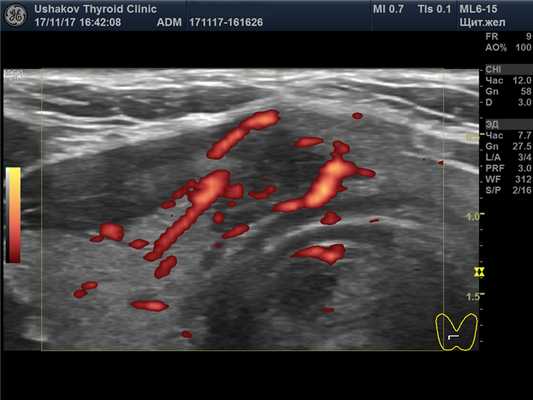

5. Неупорядоченный кровоток в узле. В допплеровских режимах УЗИ (при ЦДК или ЭДК) врач должен проверить особенности кровотока. Понятие «смешанный» кровоток не несет пользы в оценке рака узла. Смешанный кровоток (т.е. по краю и внутри узла) случается при всех узлах и поэтому не может указывать на вероятность злокачественности. Напротив, упорядоченность сосудистой сети узла может свидетельствовать как в пользу доброкачественности, так и ориентировать в вероятности рака узла. Под упорядоченностью кровотока понимается распределение сосудов преимущественно по границе сегментов (т.е. вокруг узла и внутри него в области перегородок между его частями).

| Рисунок 1. В правой части перешейка щитовидной железы узел с признаками рака: 1) неправильная форма, вытянут не вдоль, а поперёк перешейка, 2) содержит значительно гипоэхогенную ткань, 3) граница узла в некоторых участках прерывистая. Класс по TI-RADS соответствует 4С. | Рисунок 2. Этот же узел в режиме ЭДК. Кровоток узла значительной интенсивности с признаками неупорядоченности распределения сосудов. |